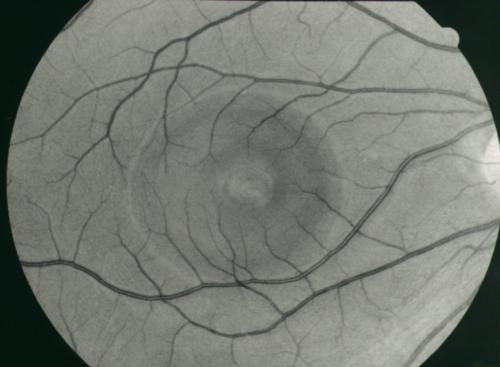

chriorétinopathie sereuse centrale

crsc2.jpg